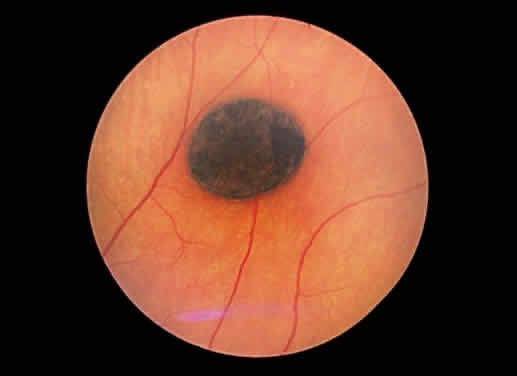

The accumulation of additional pigmentation by the pigment epithelium frequently

is accompanied by enlargement of the cell. This alteration may

be seen as a normal anatomical variant in the macula, in which the

pigment epithelium is taller and more pigmented than in other retinal

zones. The physiologic hypertrophy of the macula accounts for some darkening

of the fundus color in this area. A similar response is seen in congenital hypertrophy of the pigment epithelium15 (Fig. 47). The hypertrophy may be so prominent as to impart a jet black appearance

to the fundus focally. Congenital hypertrophy of the pigment epithelium

may be mistaken clinically for choroidal nevi and melanomas, but

the two groups of lesions are distinct ophthalmoscopically. Congenital

hypertrophy appears jet black, whereas choroidal melanocytic lesions

appear slate gray to brown-black (Fig. 48). In addition, the pigmentation within congenital hypertrophy of the pigment

epithelium may not be uniform, accounting for focal “lacunae” of “depigmentation.” Also, the borders of the congenital

pigment epithelial hypertrophy frequently are distinct and scalloped. Grouped

pigmentation of the fundus (“bear tracks”) is

another manifestation of hypertrophy of the pigment epithelium.16  Fig. 47. Fundus photograph of congenital hypertrophy of the pigment epithelium. Notice

the sharp delineation of the lesion and its jet black color. Fig. 47. Fundus photograph of congenital hypertrophy of the pigment epithelium. Notice

the sharp delineation of the lesion and its jet black color.